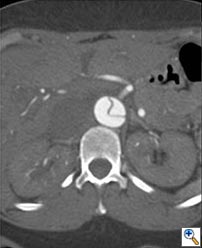

A 49-year-old woman with a history of hypertension and smoking presented to an outside hospital with sudden onset chest pain and hypotension. Computed Tomography/ Angiography (CTA) of the chest and abdomen revealed a type A aortic dissection extending from the ascending aorta to the left common iliac artery. (Figure 1) Of note, there was a significant pericardial effusion and left pleural effusion. Due to her hypotension and tamponade physiology, the patient was rapidly intubated followed by unsuccessful pericardiocentesis. The patient was then transferred to our institution for emergent dissection repair.

Figure 1a-e. Computed Tomography/Angiography (CTA) at

presentation demonstrating a type A aortic dissection.

Figure 1a. Axial CT at level of the pulmonary artery. The false lumen in the ascending aorta (white arrow) has minimal flow.

Figure 1b.

Figures 1b-d. Axial CT cuts demonstrating the dissection continuing into the left common iliac artery.

Figure 1e. Oblique sagittal CT reconstruction demonstrates the Type A dissection is complex with multiple fenestrations in the abdomen. Note bovine arch anatomy.